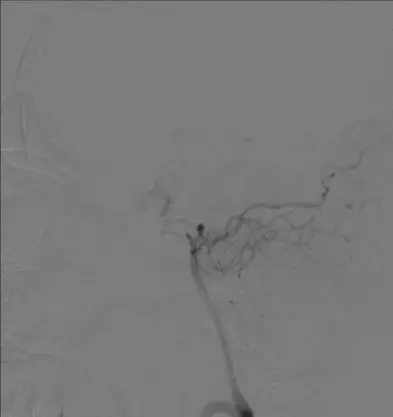

诊断分析 右侧颈内动脉C1段闭塞合并右侧大脑中动脉M1段闭塞。拟行支架机械取栓治疗。 治疗情况 耗材:8F血管鞘,8F导引导管,Navien 5F颅内支撑导管,Rebar-18微导管,0.014微导丝,Solitaire 4-20支架,SpiderFX保护伞,5-40球囊、1.5-20球囊,2-20球囊,9-40 Protégé。 支架: 1. 开通右侧颈内动脉C1: 通过1.5以及2.0球囊对C1段依次进行扩张,可见C1重度狭窄。

5mm Spider保护伞到位。

通过5.0mmX40mm球囊扩张C1段,恢复颈内动脉血流。